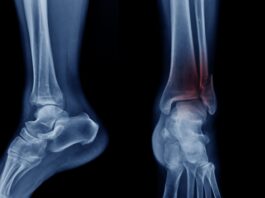

Frattura di caviglia: benefici della crioterapia di terza generazione preoperatoria

Abbastanza frequente tanto tra gli anziani, quanto tra i giovani, le fratture di caviglia vengono spesso trattate con...